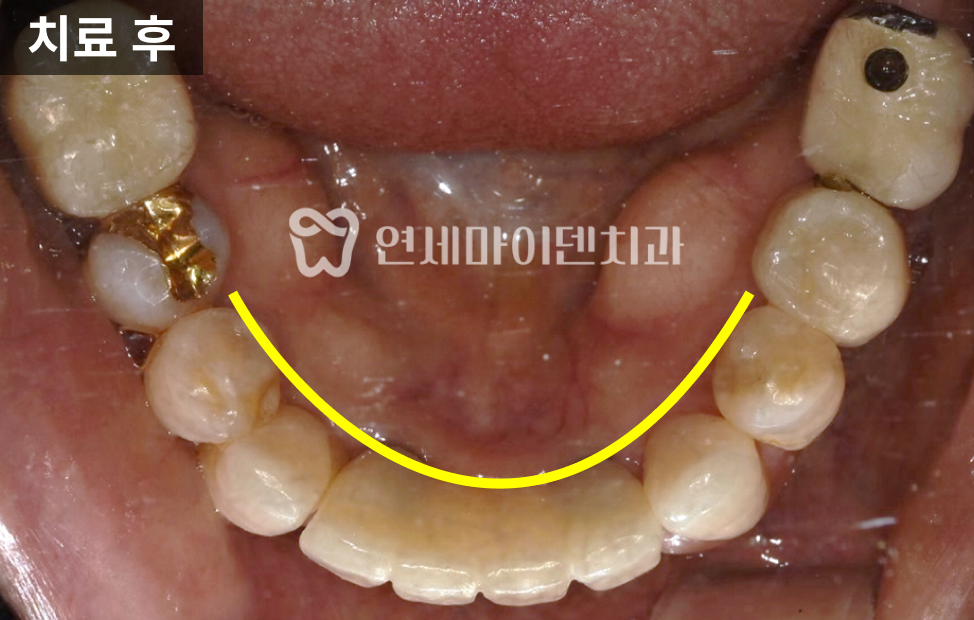

정면에서 보면

위 앞니보다 아래 앞니 노출이

더 많은 상태임을 확인할 수 있었습니다.이번 치료의 핵심 목표는

다음 두 가지였습니다.- 전치부, 특히 앞니의 돌출을 개선하는 것

- 위 앞니의 노출 비율을 늘려 외관상 나이가 들어 보이지 않도록 하는 것

치료 후

앞니는 약 5mm 내외로 후방 이동되었고,

위 앞니의 노출 비율이

이전보다 증가한 것을 확인할 수 있었습니다.어금니에서 교합이 안정적으로 지지되고,

전치부는 발음, 심미, 절단 기능을

균형 있게 수행하고 있었습니다.

측면에서

코–입술–턱 끝을 잇는 라인을 확인해도,

전치부가 후방으로 이동하며

입술 돌출이 완화된 모습이

객관적으로 확인되었습니다.